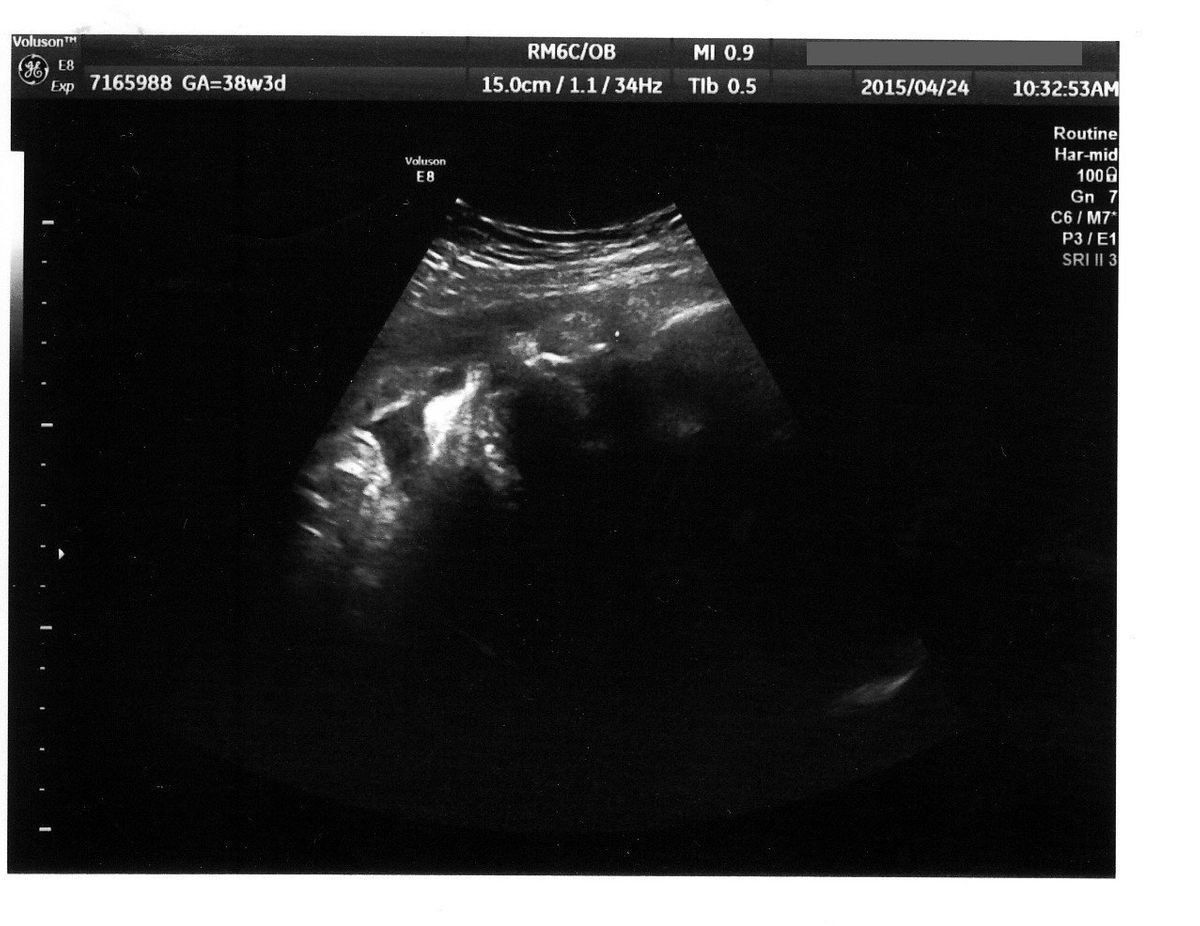

出産直前! - 妊娠38週目のエコー写真

出産前日のエコーです。真ん中の薄い線が背骨、上のところが腰だと思います。この頃は、赤ちゃんの頭は私の骨盤の方にあり、顔を見ることはできませんでした。

赤ちゃんの体重がまったく増えなくなり、37週で管理入院することになりました。赤ちゃんの推定体重は2000g程度で、誤差を含めると2000g以下の可能性もあり、低体重児になってしまいます。ちょうどよく大型連休に入り、夫が家で上の2人の子どもの面倒を見ることに。病院の食事は薄味だけどおいしくて、カロリー計算も完璧。赤ちゃんの体重を増やそうとたくさん食べていた私ですが、入院中に2kgやせてしまいました。

そして、入院7日目の朝に陣痛が開始。そのままお昼の12時に出産しました。3人目だけあって、陣痛から出産まではスムーズ。推定体重が2000g前後だと言われていた赤ちゃんでしたが、生まれてみると2600g以上あって、医師も私もびっくり。赤ちゃんは用意されていた保育器に入りましたが、特に異常もなく、翌朝には普通のベビーベッドに移されました。

遠くの大学病院まで転院しましたが、特別な医療行為の必要なく、妊娠38週3日に、体重2682g、身長46.5㎝で、頑張って生まれてきてくれた赤ちゃん。出産までヤキモキしましたが、無事に生まれてきてくれたことに本当に感謝の気持ちです。そして、上の子2人と夫は、濃密な3人だけの大型連休5日間を過ごし、きずなも深まりました。4人目は考えていないので、これが最後の出産となりそうですが、ちょっと特別な体験になりました。